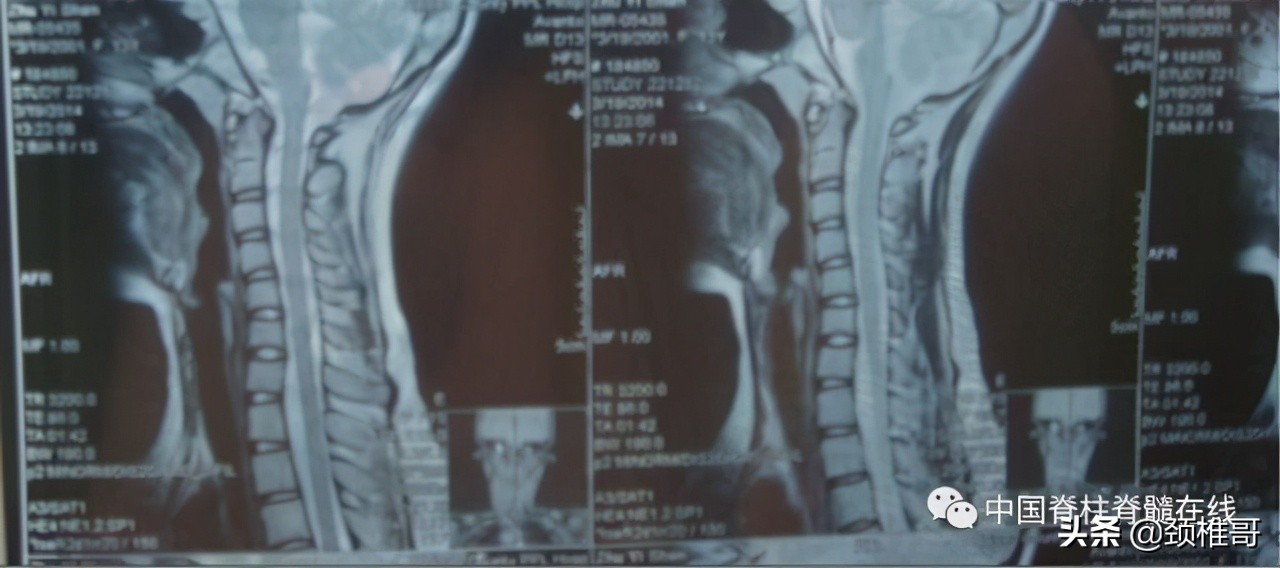

交感神经型颈椎病患者:颈椎MRI颈椎间盘正常、颈椎生理曲度异常

颈椎正侧位:序列 欠佳 动力位:颈椎3-6各个节段之间不稳

很多病人都是这样:椎间盘没有问题,但是有明显的颈椎不稳。或者即使某个节段发生了椎间盘的膨出或者突出,然而椎间盘膨出或突出的节段并不一定是最为不稳定的节段。